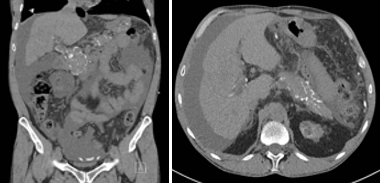

Figure 2.Doppler echocardiography revealed a severe transvalvular aortic regurgitation.

A FibroScan with a fibrosis score of F2 indicates moderate liver fibrosis. A gastroscopy confirmed the presence of varicose veins and global gastropathy due to portal hypertension. A Holter monitor did not reveal any arrhythmia. The patient was put on oral furosemide and spironolactone. Given that the ascites was recurrent despite optimal drug treatment, a multidisciplinary staff considered placing a transjugular intrahepatic portosystemic shunt (TIPS). The pre-intervention trans-thoracic and trans-esophageal echocardiogram ( Figure 2) unexpectedly showed a severe aortic regurgitation due to degenerative valve disease and a dilated left ventricle (Vtd 208,2ml with norms 50-90 mL/m2) with preserved left and right ventricles ejection fractions, without dilated right cavities and without pericardial effusion. The patient had his aortic valve replaced by a mechanical valve almost one year after his transplantation. Our patient underwent 1 episode of staphylococcus aureus peritonitis with evidence of tunnelitis. He had to be hospitalized for IV vancomycin and cephalosporine. A final 350 ml of ascitic fluid was removed 12 months after kidney transplantation. The PD catheter was removed 4 months later. The patient did not relapse his ascites in 3 years.